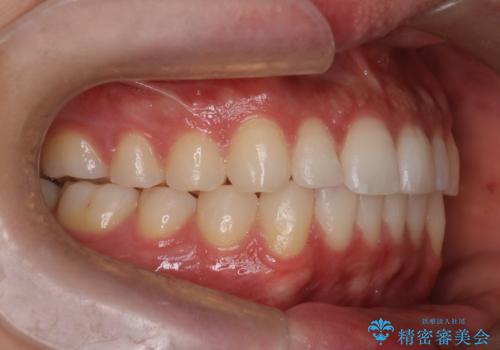

- 前歯の歯並びの改善を希望され来院された患者様です。

初診時の歯並びの状態としては、上下ともに前歯部の中等度以上のがたつき(叢生)があり、右の前歯が1本飛び出した状態でした。

抜歯は行わず上下顎ともに、主に歯列弓の拡大とディスキング(歯と歯の間に隙間を作る処置)を行い叢生を改善しました。

見た目、嚙み合わせ及び、治療期間や施術内容に大変ご満足いただきました。